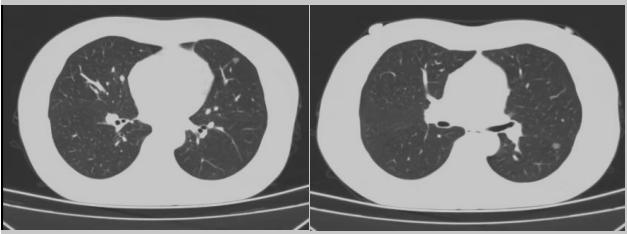

病例一:70多歲的患者王先生于2020年“急性心梗”入院時(shí)檢查發(fā)現(xiàn)了肺部結(jié)節(jié),王先生沒(méi)有在意,其間未規(guī)范復(fù)查胸部影像學(xué)檢查,于2023年2月份再次發(fā)作心絞痛時(shí),發(fā)現(xiàn)肺結(jié)節(jié)已發(fā)展成直徑約2.5cm實(shí)性腫塊,患者在家長(zhǎng)期口服“替格瑞洛及腸溶阿司匹林”等抗凝藥物,生活可自理,于冠狀動(dòng)脈二次植入支架后三個(gè)月,收住市二院胸外科,經(jīng)心內(nèi)科、麻醉科等多學(xué)科會(huì)診后,由胸外科主任王松陽(yáng)、副主任醫(yī)師薛飛及科室團(tuán)隊(duì)行“單孔胸腔鏡下左上肺癌根治術(shù)”,術(shù)后結(jié)合快速康復(fù)理念,三天后拔除胸管,一周出院。